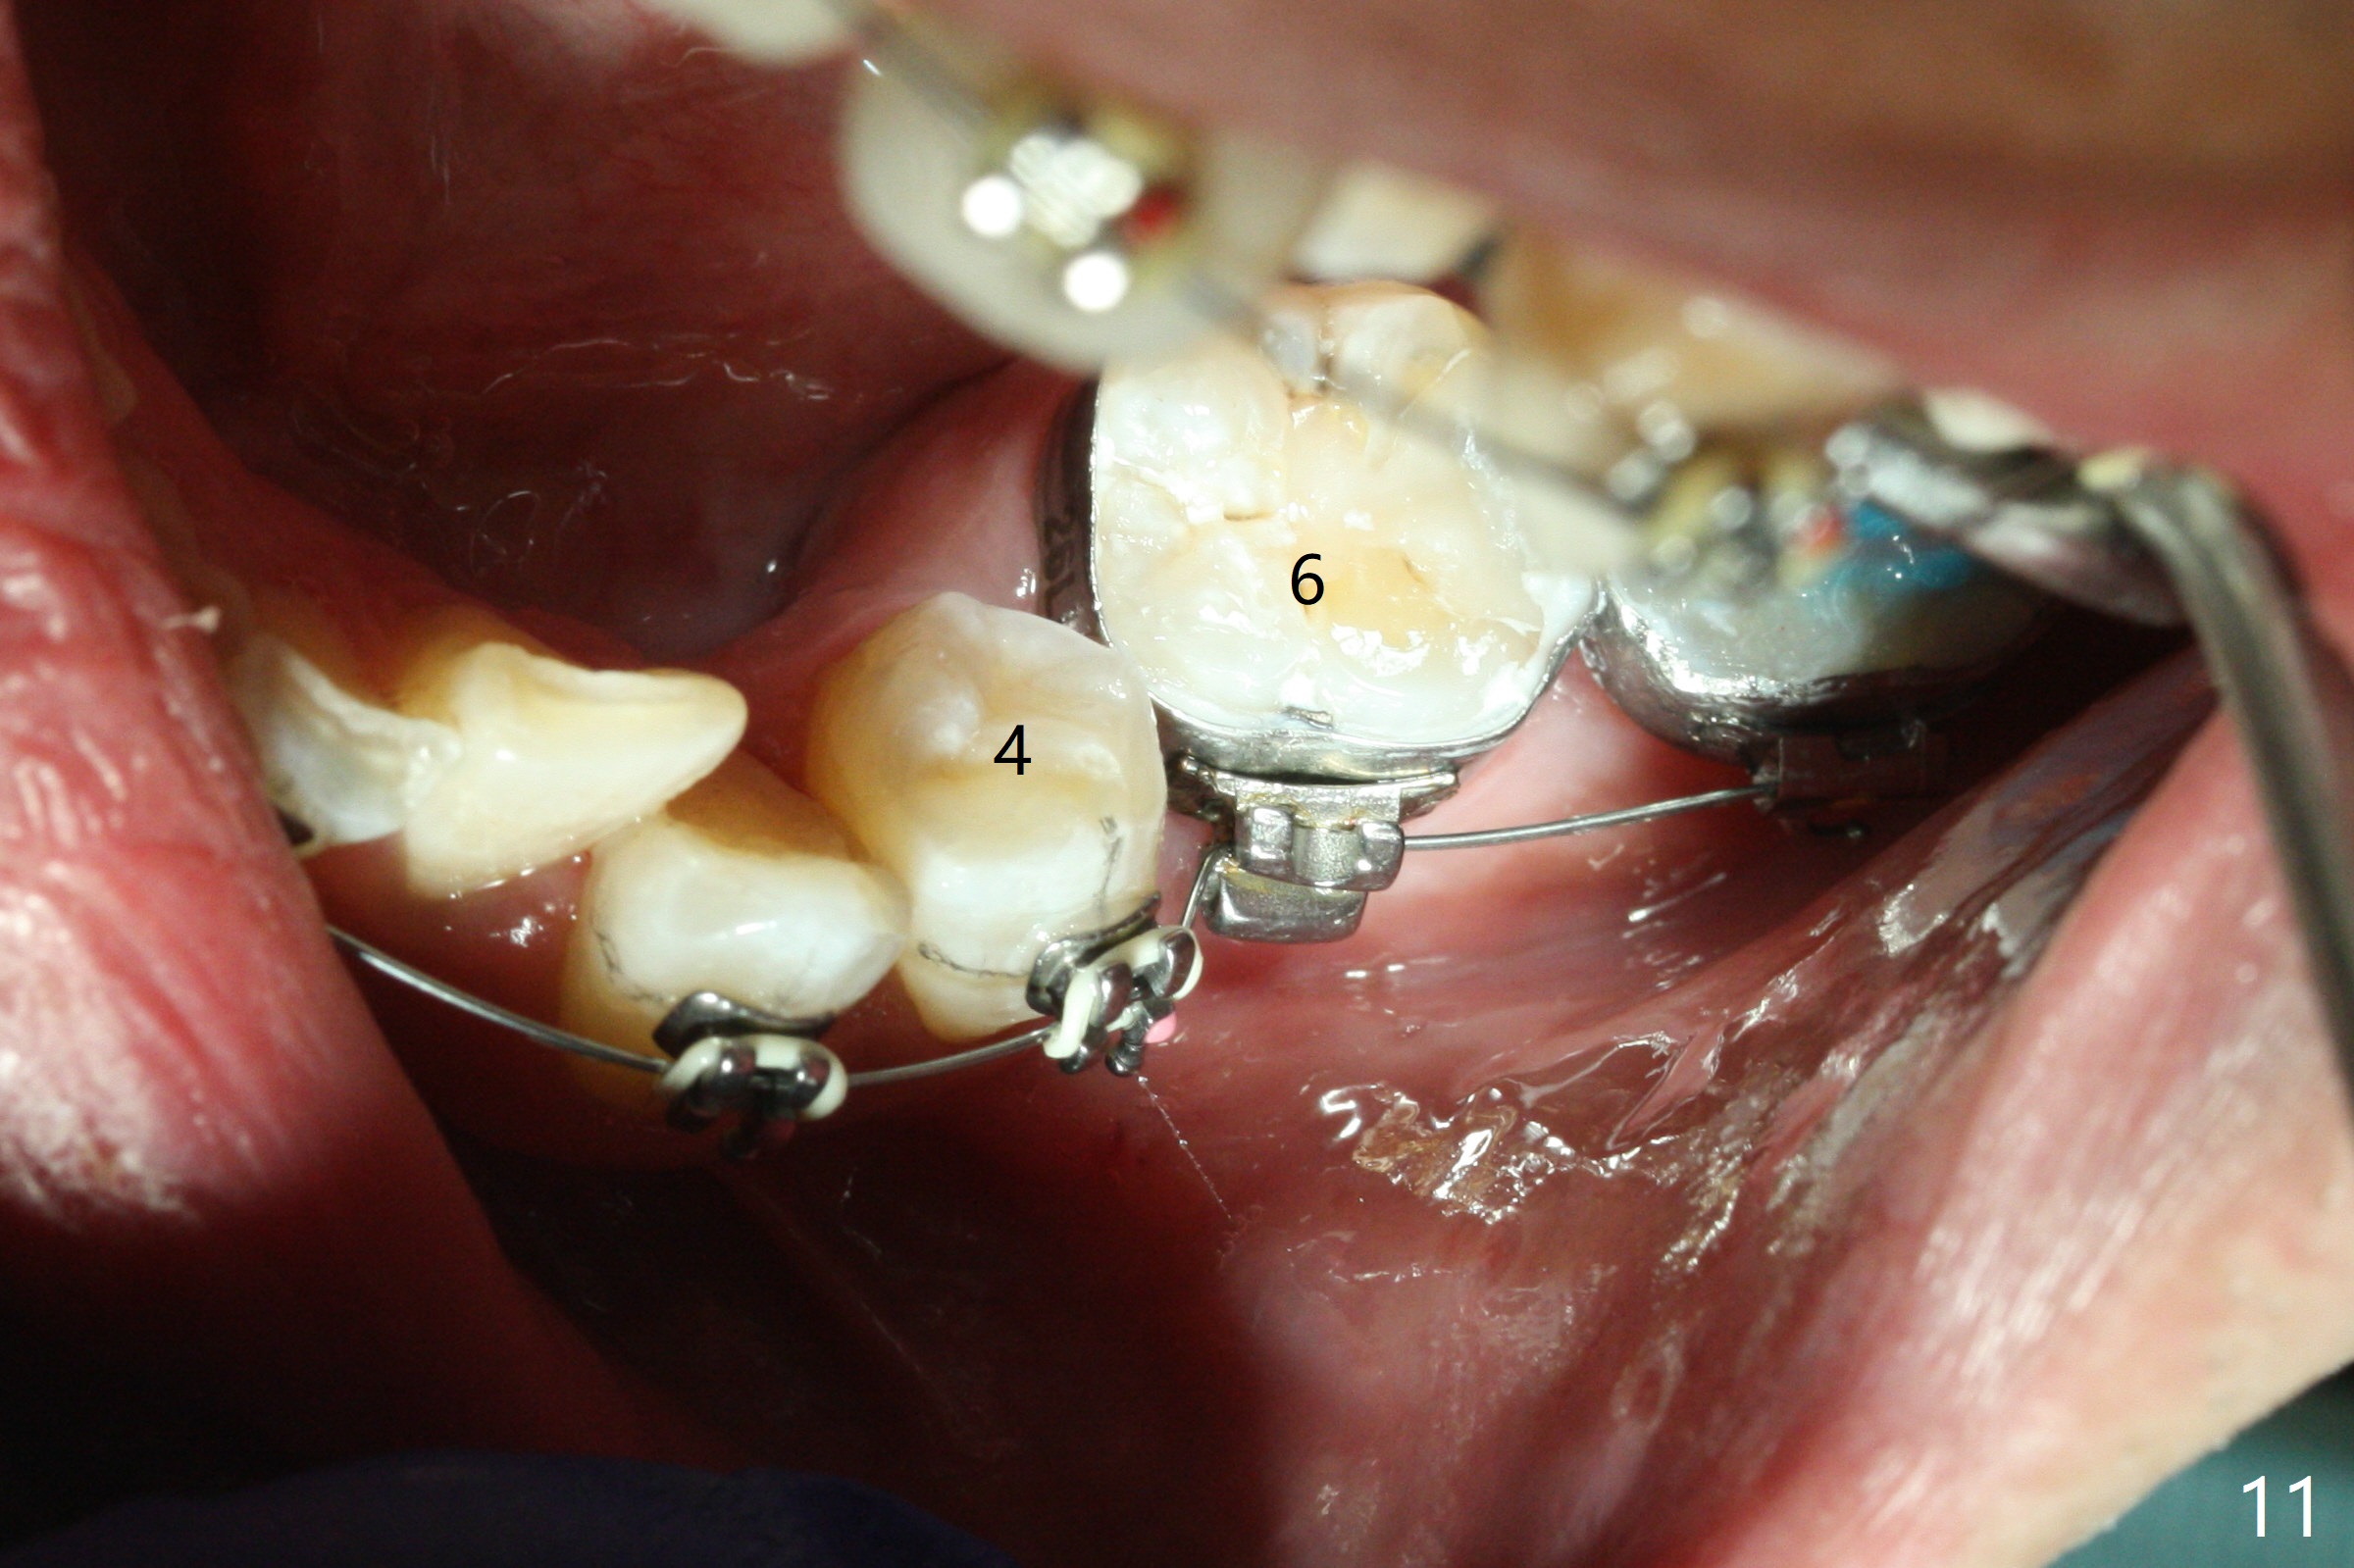

Severe crowding (Fig.1-7) appears to be alleviated especially 2 months after UR5 extraction. Diastemata seem to form mesial and distal to UR2 (Fig.8). Because of severe wear at UR3 (Fig.6), there is no bracket placement differential around it (Fig.8 (14 niti wire)). Lower bands and brackets are placed a week later (Fig.9-11). Because of tight space between LR4 and the opposing tooth (Fig.10), band adhesive is applied to L7 occlusal surface to open the bite (Fig.9). There is an abrupt kink of 12 niti wire between LL4 and 6 (Fig.11). The latter does not improve much in a month; the wires remain the same (Fig.12). For LL2, LR4 has been retracted for ~ 1 month (Fig.13). There is mild tension when 18 ss wire is inserted between LL4 and 6 five point five months post banding (Fig.14). UR4 has been distalized for a month using buccal power chains x3 resulting in rotation; to counter the rotation, a lingual button is placed with power chain x3 lingual and x2 buccal (Fig.15). With space gaining, it is time to finish definitive filling (Fig.16 *). Next visit check midlines, overjet, interdigitation, and molar classification. R4s distalize, but associate with rotation because of power chains buccal and lingual 8 months post banding (Fig.17,18). With the use of the same wires, power chains are applied lingual to continue distalization and rotation correction (Fig.20,21). Lingual buttons are placed at L2s buccalization (Fig.19) and mesialization (Fig.22,23). It appears that space should be created distal to LR3. That is that the lower anterior teeth should be shifted to the right, although it may be not appropriate for the midline.